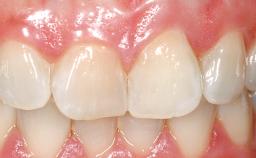

A 30-year-old female patient had lost tooth 21 and was referred to our clinic for consultation and treatment. Due to advanced apical infection, tooth 21 had been extracted two months earlier at another clinic and an acrylic-resin tooth had been bonded to the adjacent teeth. The patient desired implant treatment to avoid any damage to the adjacent natural teeth. While the patient had no history of any systemic disorder, she was a heavy smoker and exhibited medium to advanced periodontitis in the entire jaw. After the initial treatment to achieve a pocket probing depth of less than 4 mm and no bleeding on probing, a decrease in the height of the papillae mesial and distal to the extraction site and overall gingival recession were observed.

Prosthesis Type FDP

Defining Characteristics One missing tooth to be replaced by an implant-borne crown

Esthetic Risk High